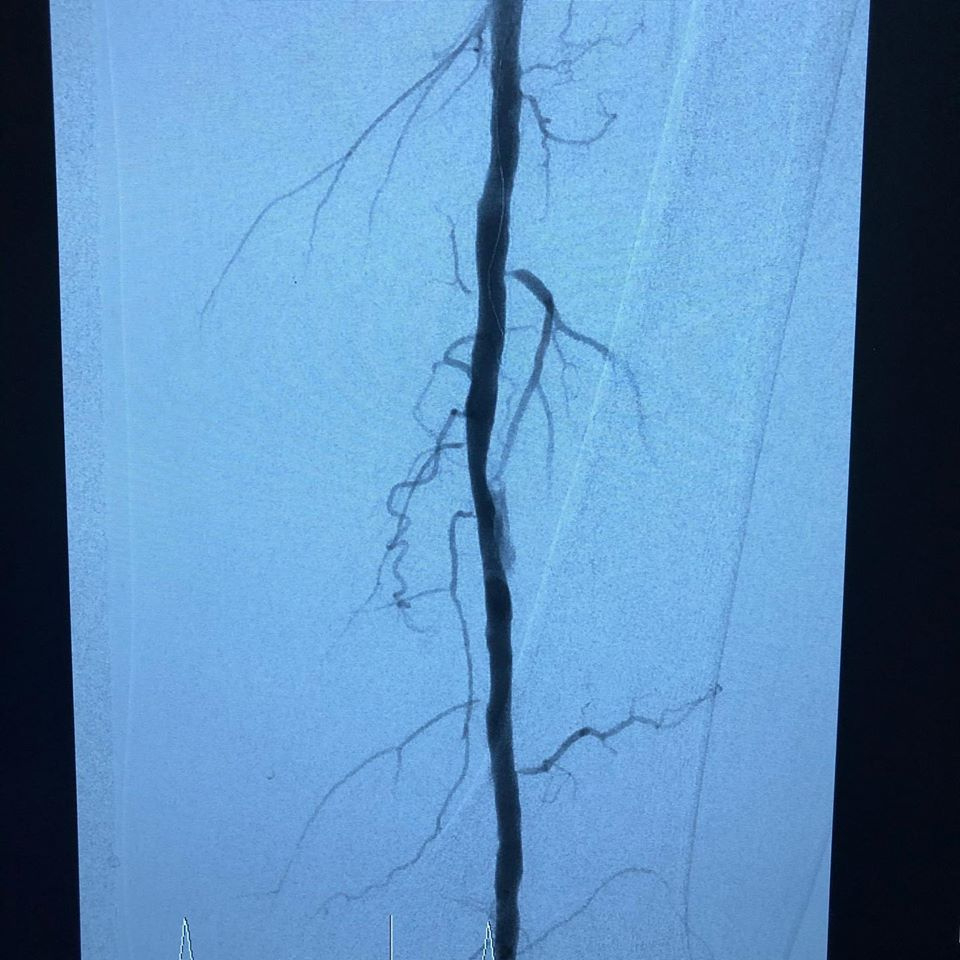

Se pasa a Hemodinamia donde se observa lesiones estenoticas en arteria poplitea y sin vasos tibiales, recanalizando en arteria pedía

(FP2, IP4, P2 GLASS 3) y se realiza angioplastia poplitea y de tibial anterior, mejorando el flujo distal, se realiza amputacion de falange distal del dedo y se observa buena evolución 24 hrs después sin complicaciones con alta a su domicilio